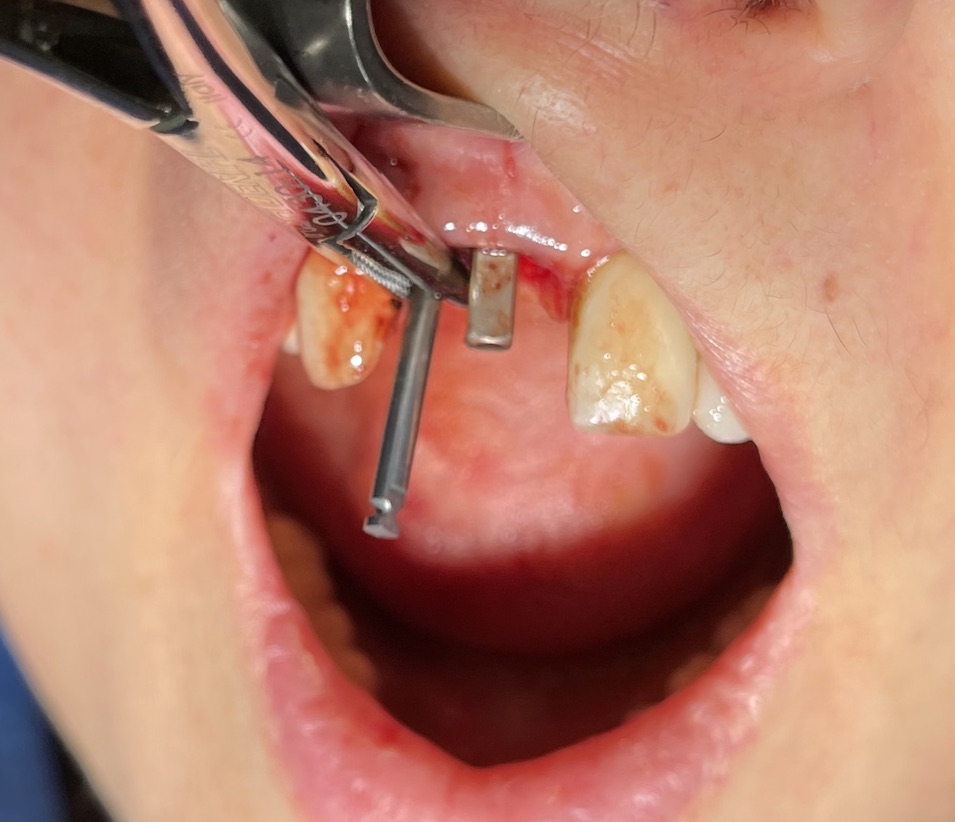

Zona dentale: 11 12

Situazione estrattiva: postestrattivi immediati

Sequenza frese: solo lanceolata

Sequenza maschiatori: diametro 4 mm

Descrizione intervento

Complicanze: assenti